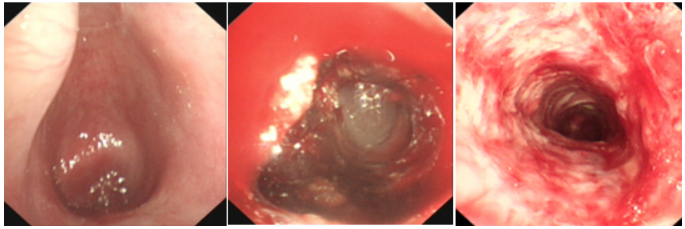

病例1:危重的良性气道狭窄

一般情况:患者女性,37岁,气管插管后气道良性狭窄,气管切开状态。

前期治疗:气管镜下冷热消融及球囊扩张治疗无效(图5);耳鼻喉头颈外科行T管置入术,置入后T管下端肉芽组织增生(图6);再次冷热消融治疗后出院,未定期随诊;T管下段增生明显(图7),病情突然变化。收入RICU,组织全院MDT。

图片

图5  气管镜下冷热消融及球囊扩张治疗

图6  T管置入术后出现狭窄和肉芽组织增生

图7  T管远端大量肉芽组织增生